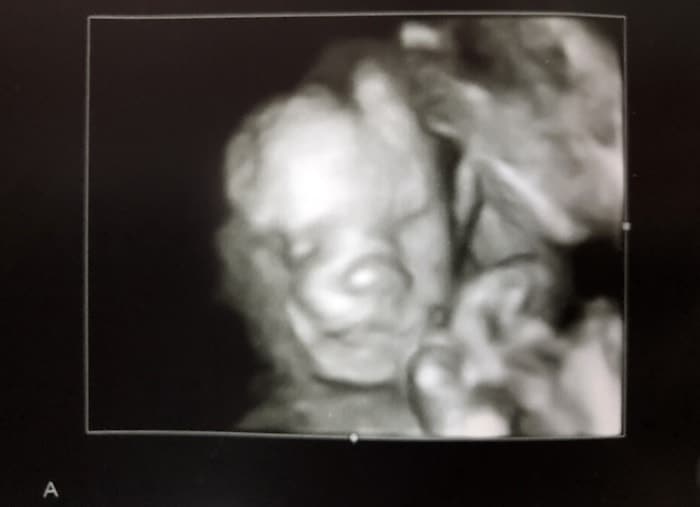

Ultrasound Photos at 21 Weeks Pregnant With Twins